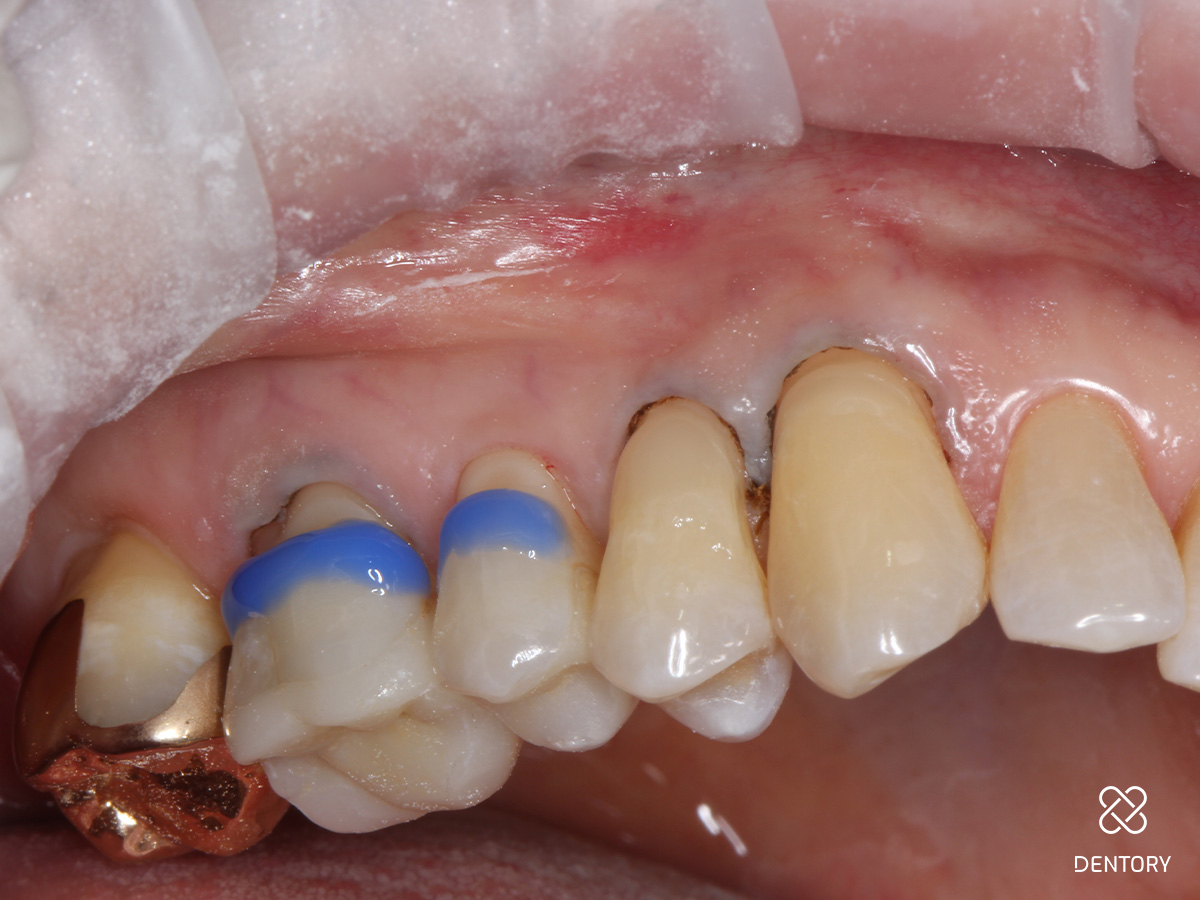

Abbildung 1

Ausgangssituation: Generalisierte Zahnhalsdefekte im Oberkiefer